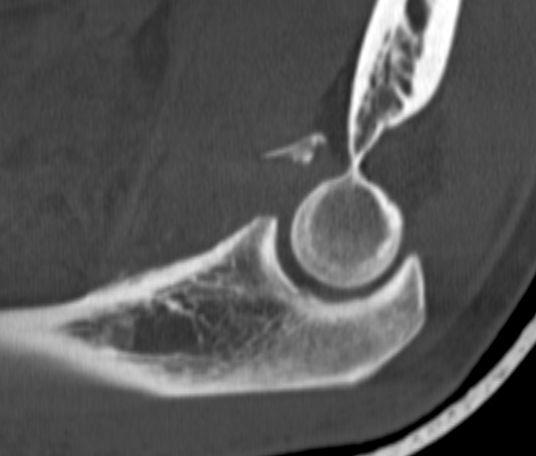

O'Driscoll classification anteromedial coronoid facet fractures

| Type I | Type II | Type III |

|---|---|---|

| Transverse fractures | Anteromedial facet fractures | Basilar fractures |

| Lasso suture fixation |

Lasso suture fixation - small Medial buttress plate / screws - large |

Dorsal +/- medial plate |

Anteromedial coronoid facet fragment

- associated with varus posteromedial rotational force

- associated with tear of lateral ulna collateral ligament (LUCL)